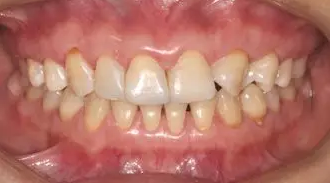

術(shù)前全牙弓咬合照

術(shù)前全牙弓非咬合照

術(shù)前上前牙正面照

口腔衛(wèi)生尚可,牙齦正常。11,12,21,23 牙體完整,散在間隙,13、24、33、34 頸部楔形缺損,探診無(wú)明顯不適,叩(-),無(wú)明顯松動(dòng)。冷熱刺激無(wú)明顯不適。22 缺失。上下牙咬合穩(wěn)定,覆 覆蓋正常。